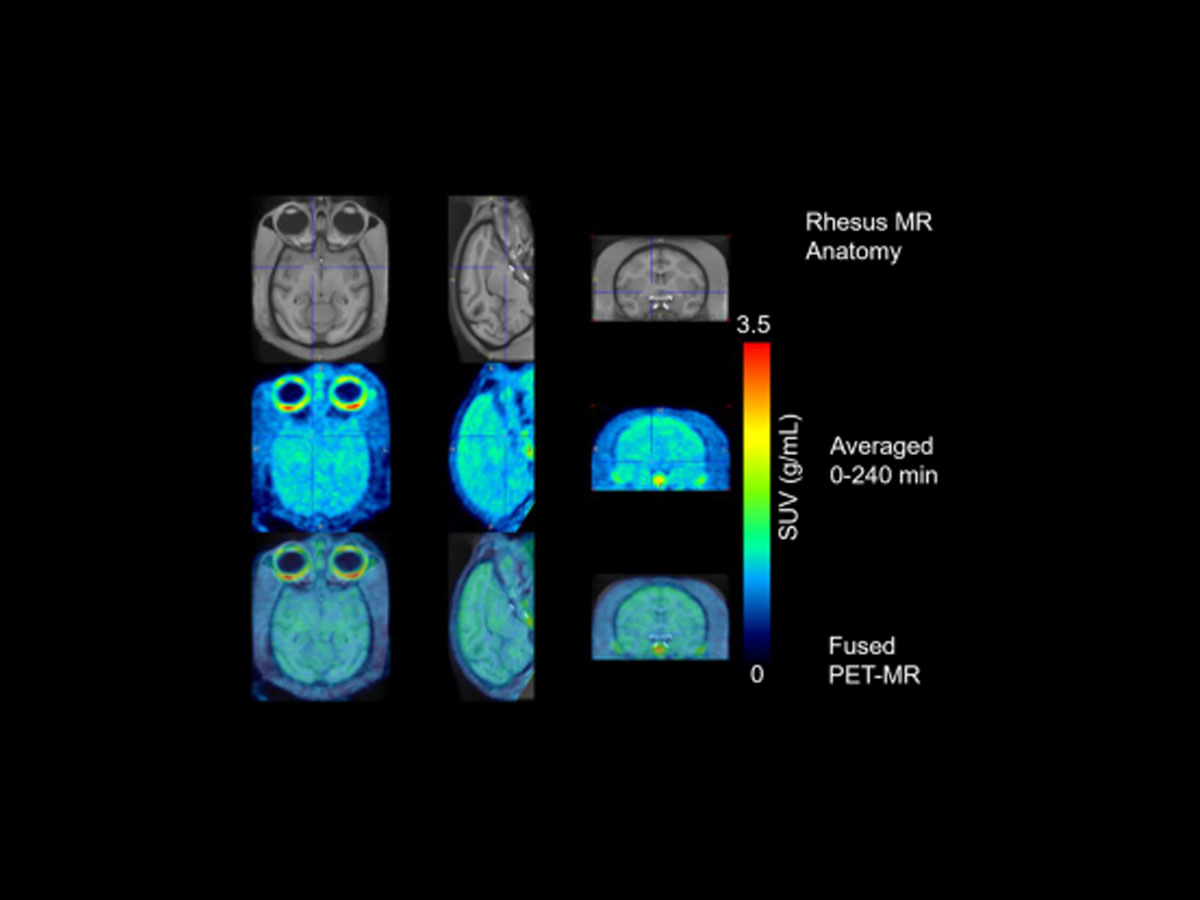

This research introduces [¹⁸F]JNJ-CSF1R-1, a high-affinity PET tracer designed to quantify CSF1R — a key biomarker of microglial activation. Through LPS and AppSAA knock-in mouse models and non-human primate imaging, the study demonstrates robust brain uptake, disease-relevant signal elevation, and strong correlation with CSF1R protein levels. These findings position the tracer as a promising tool for therapeutic monitoring, biomarker validation, and early-phase neuroinflammation studies.